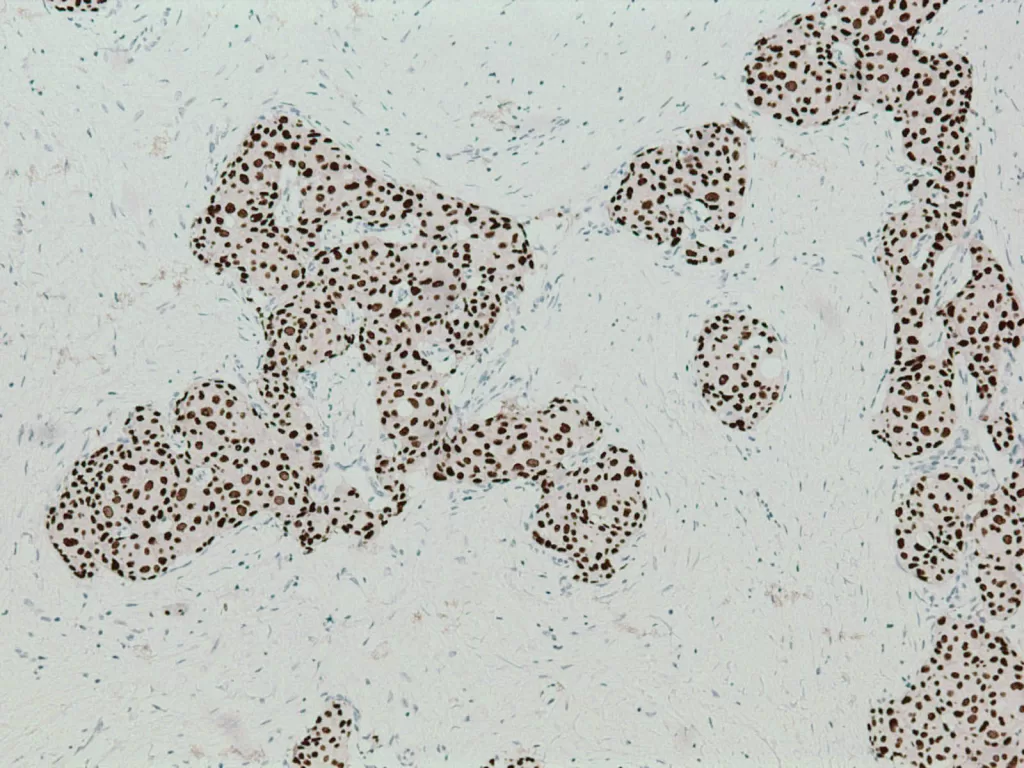

ER(雌激素受體):讓我們知道癌細胞是否依賴雌激素而活。若為陽性,可以用荷爾蒙治療像關掉電源般,讓它靜下來,不再被過度刺激。

PR(黃體素受體):與 ER 類似,是另一種荷爾蒙訊號的開關。當 PR 也為陽性時,意味著癌細胞較願意「聽話」──這時可以採用更溫和的治療方法。

當妳做完乳房攝影或超音波,那一小片被切下的組織會進入顯微鏡的世界。病理醫師在那裡看見平常看不見的部分,那些色彩、結構與節奏,試著從中解讀身體的語言。最後的病理報告不僅僅是診斷,更是傳達了妳的身體在說什麼、帶來了怎麼樣的希望。